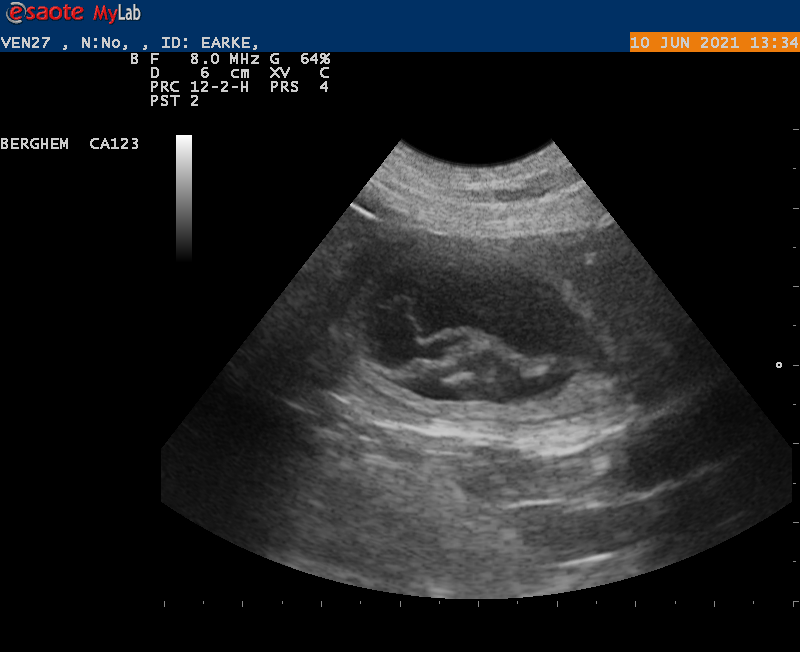

Goed nieuws!

10-6-2021

Vanmiddag zijn we naar de dierenarts geweest met Earke voor een echo. Super goed nieuws: Earke is drachtig. We hebben zelfs al de hartjes zien kloppen van de pups.

Als alles goed blijft gaan krijgen we rond 14 juli een nestje van Earke en Douwe.